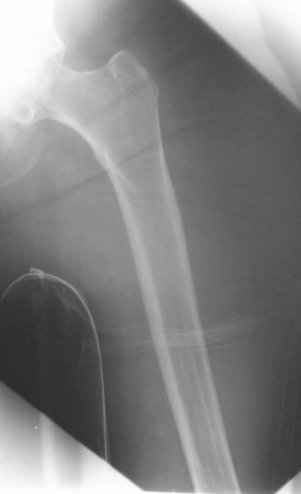

Go antegrade if you have an approriate implant available. Attached is a result of a similar fracture.